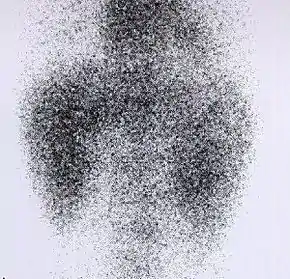

DMSA scan

![]() Decreased Tc99m-DMSA uptake in both kidneys, suggestive of renal failure. | |